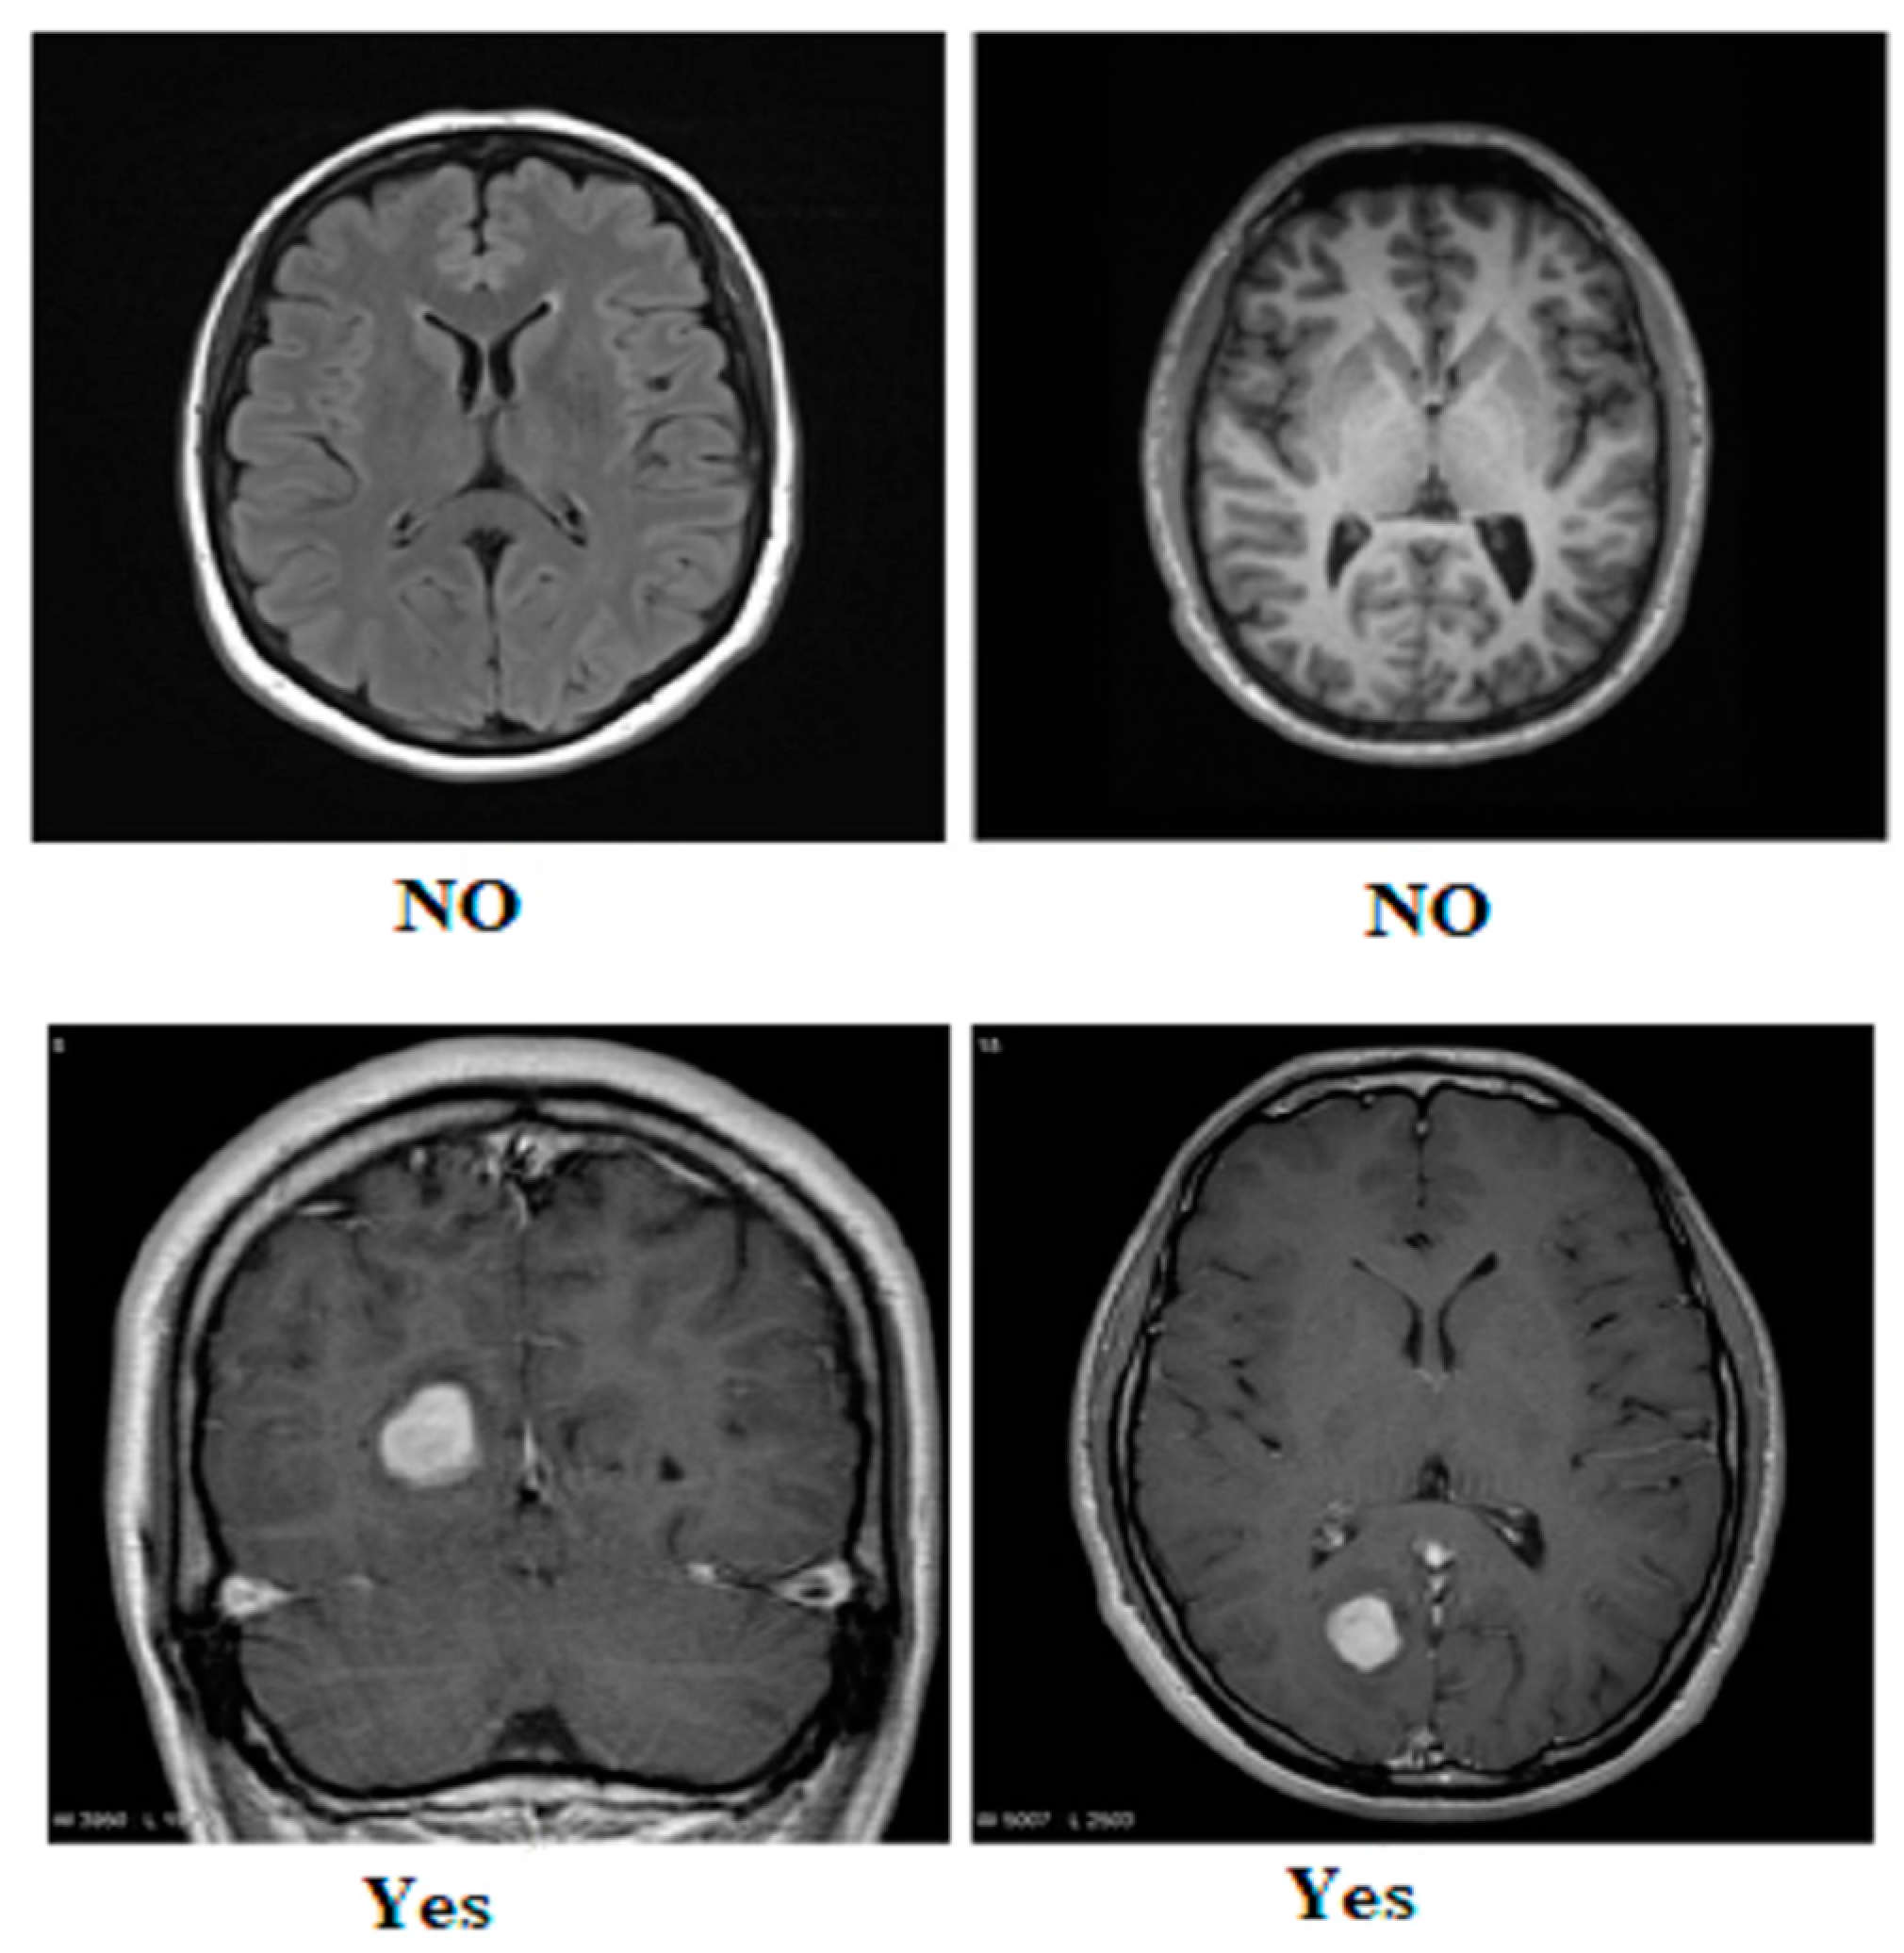

3.1. MRI Dataset

| Glioma | 1621 | 1321 | 300 | Yes | 155 | 135 | 20 | Yes | 1500 | 1200 | 300 |

| Meningioma | 1645 | 1339 | 306 | No | 84 | 66 | 18 | No | 1500 | 1200 | 300 |

| Pituitary | 1757 | 1457 | 300 | ||||||||

| No Tumor | 2000 | 1595 | 405 | ||||||||

| Total | 7023 | 5712 | 1311 | Total | 239 | 201 | 38 | Total | 3000 | 2400 | 600 |